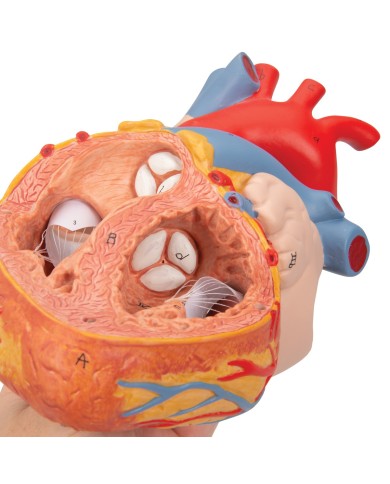

Modello anatomico di cuore, ingrandito 2 volte, su cavalletto

Questo modello dettagliato mostra, oltre alle strutture anatomiche del cuore, anche una parte del diaframma (base)